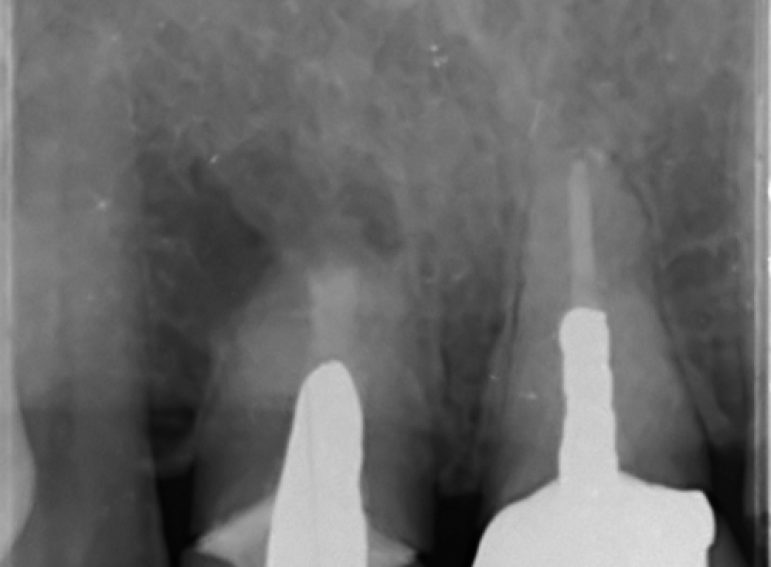

Case 26 – Endodontics

Repeat apicectomy with grafting